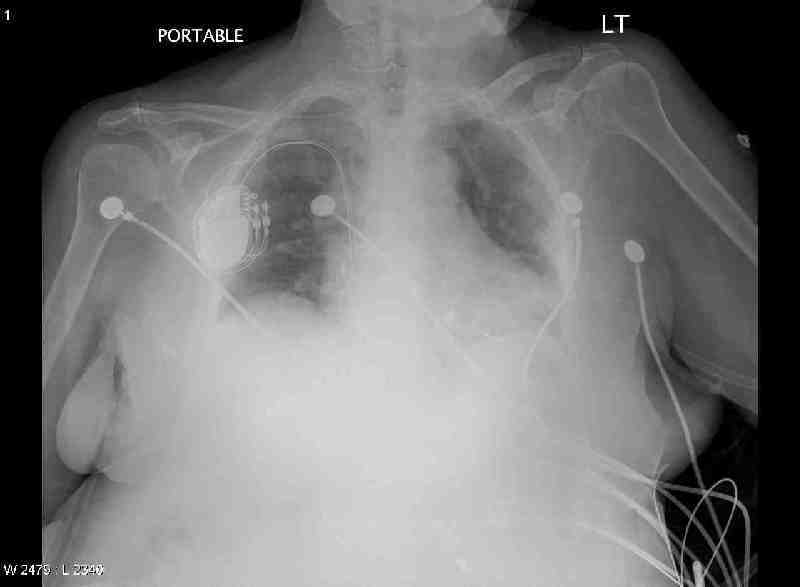

CXR Day 1

Study Description: CHPORT

Reason for Study: POST OP PACEMAKER

Clinical History: Postoperative pacemaker placement

Technique: A portable AP view of the chest was obtained.

Comparison: None

Findings: A pacing device is situated over the right anterior lateral chest wall. The pacer leads are situated over the right atrium and ventricle. There is pulmonary vascular congestion.

Impression: Pulmonary vascular congestion. Dual lead pacemaker placement as above.